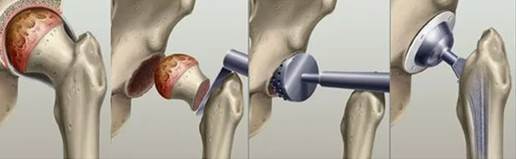

Остеосинтез — это хирургический метод лечения переломов и восстановления целостности костей.

Рисунок 1. Остеосинтез

Суть метода. В ходе операции врач:

- Сопоставляет (репонирует) костные отломки — возвращает их в анатомически правильное положение;

- Прочно фиксирует фрагменты с помощью специальных конструкций: штифтов, спиц, винтов, пластин или аппаратов внешней фиксации.

Основные виды остеосинтеза:

- Наружный — над поверхностью кожи устанавливают специальную конструкцию (аппарат Илизарова) и вводят через кость спицы, которые крепятся на кольцах снаружи конечности для фиксации кости [5].

- Внутренний — специальные конструкции удерживают костные отломки внутри тела на кости (накостный остеосинтез — с помощью пластины) или внутри самой кости (погружной способ — с помощью спиц, винтов, гвоздей, штифтов) [8]. Устанавливается непосредственно в зоне перелома и далее зависит от ряда клинико-анатомических и биомеханических факторов: локализации перелома (косая, поперечная, винтообразная, оксольчатая), степень смещения отломков, состояния костной ткани (при остеопорозе прочность фиксации снижается), выраженности повреждения окружающих мягких тканей [1].

Выбор конкретного способа внутреннего остеосинтеза обусловлен необходимостью обеспечения оптимально стабильной фиксации и условий для репаративной регенерации кости [7]. Интрамедуллярный остеосинтез чаще применяется при переломах длинных трубчатых костей, поскольку позволяет равномерно распределять нагрузку вдоль оси кости [2].

- Интрамедуллярный (внутрикостный) — штифты, гвозди или стержни вводятся в костномозговой канал кости;

- Экстрамедуллярный (накостный) — пластины крепятся к поверхности кости винтами;

- Чрескостный — фиксаторы вводятся под углом к оси кости (наклонно или поперечно);

- Комбинированный — сочетание нескольких методов фиксации;

- Ультразвуковой — костные фрагменты склеиваются с помощью ультразвука и специальной мономерной смеси, которая образует биополимерный конгломерат [5].